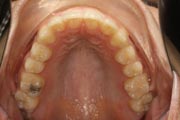

Crowding

After